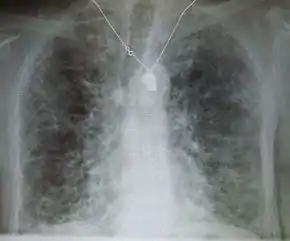

| End-stage pulmonary fibrosis of unknown origin, taken from an autopsy | |